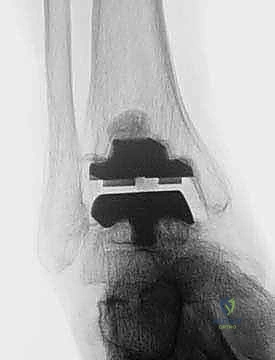

TECH FIG 5 • Subtalar arthrodesis. A. Postoperative AP view with subtalar arthrodesis using a single OA cancellous screw.

TECH FIG 5 • Subtalar arthrodesis. B. Lateral view.

FIG 6 • The TNK ankle replacement for rheumatoid arthritis of the ankle (cemented replacement). A. Preoperative AP view. B. Preoperative lateral view. C. Postoperative AP view 2 years 6 months after the surgery. D. Postoperative lateral view.